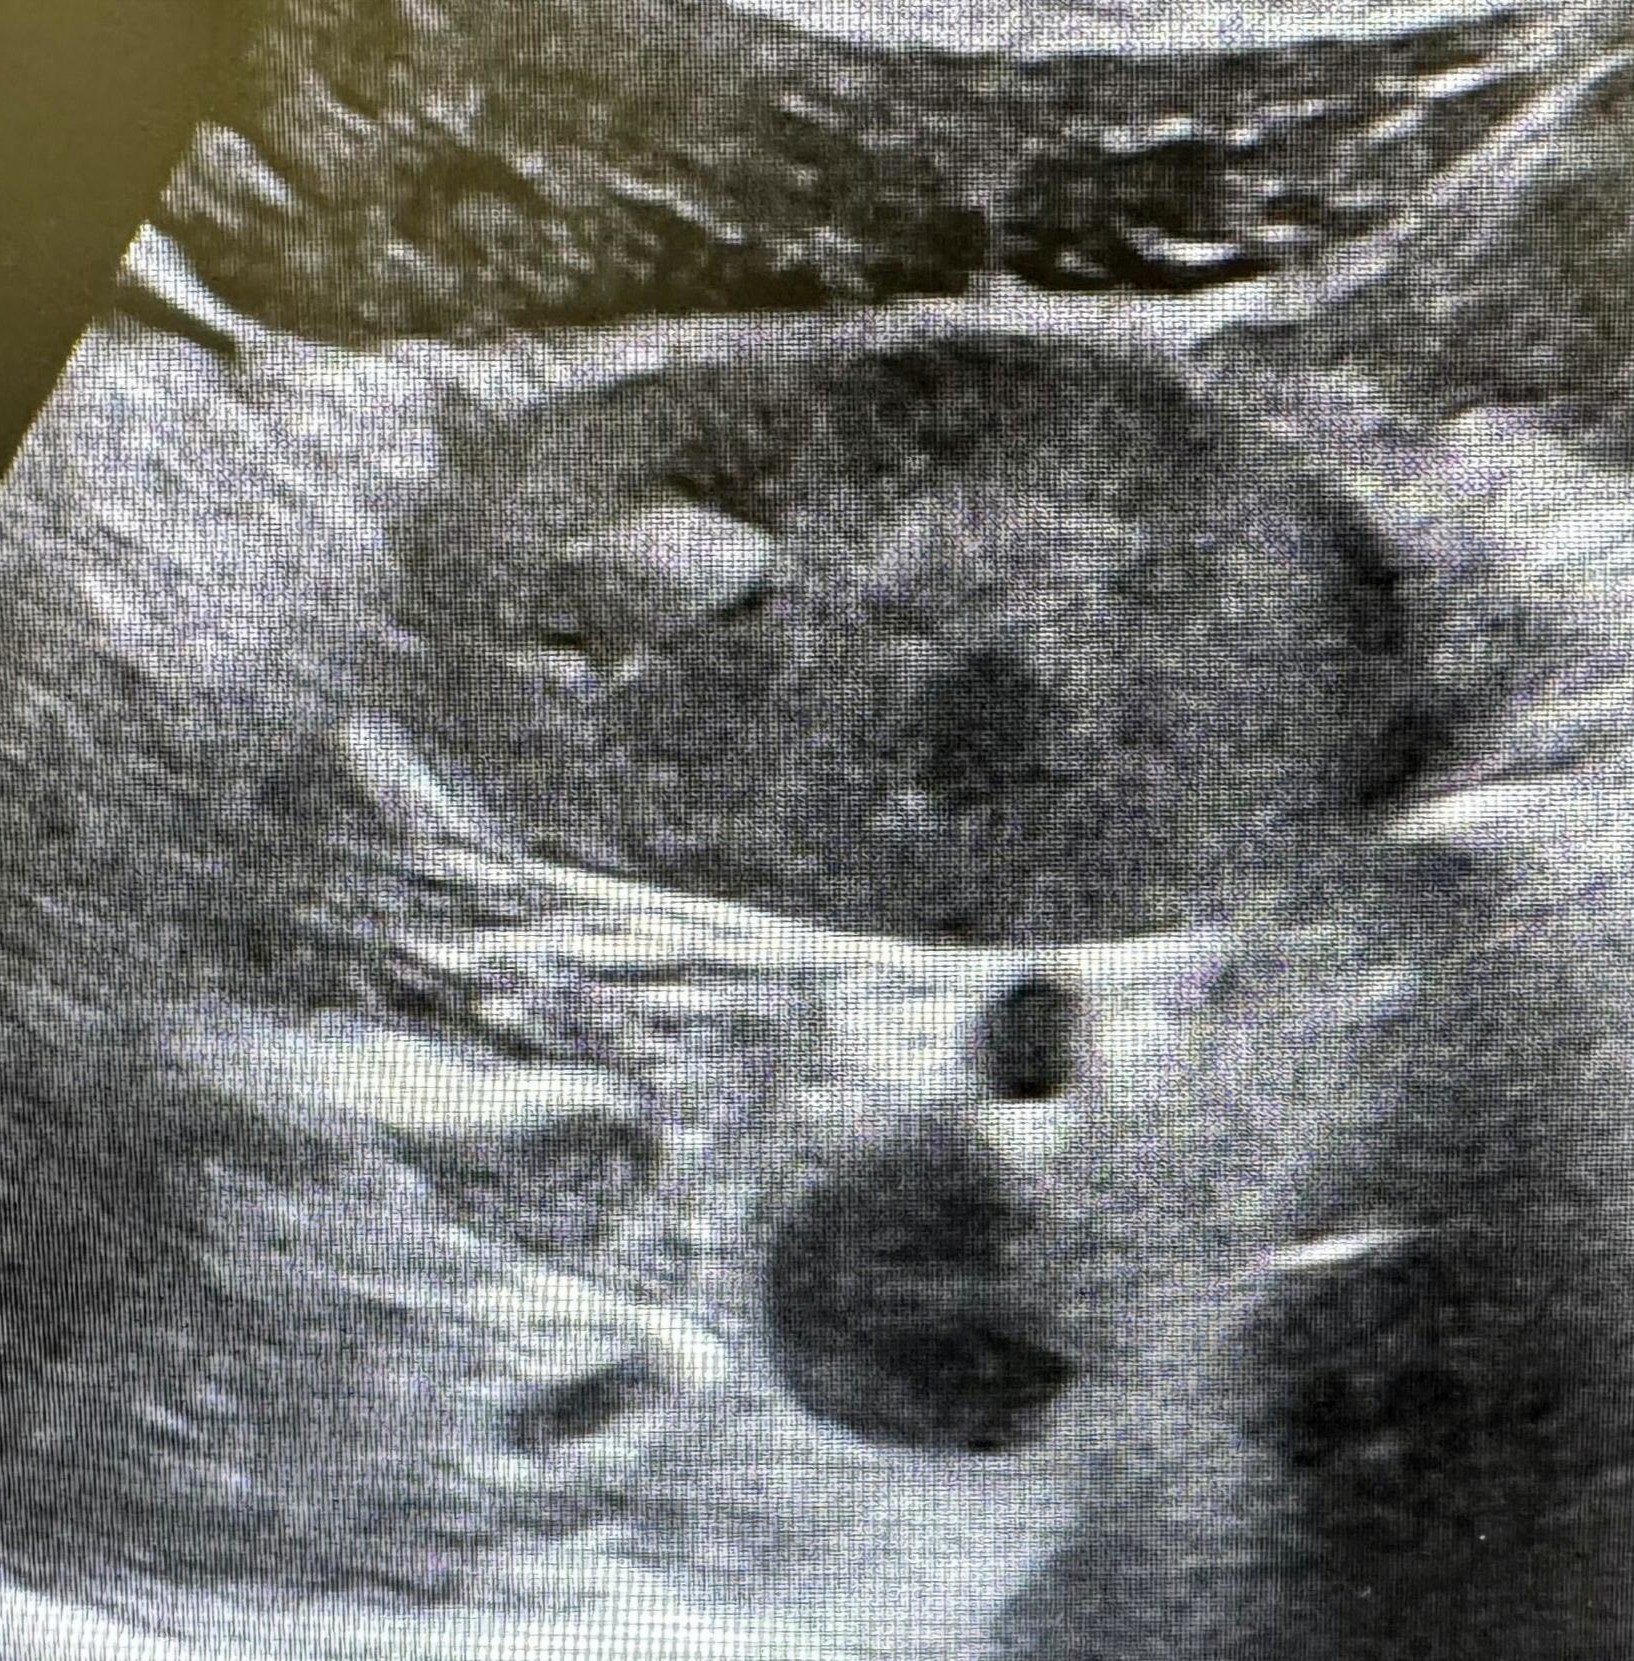

Se realiza eco abdominal: Riñón derecho ectopico, de localización paraórtica derecha, anterior a las asas intestinales, con pelvis renal orientada hacia anterior, de tamaño y grosor cortical normal, sin hidronefrosis. Riñón izquierdo de localización, morfología y tamaño normal, con buena diferenciación cortico-medular. Sin dilatación de la vía urinaria.

Conclusión: riñón derecho ectópico, congruente con la masa palpable.